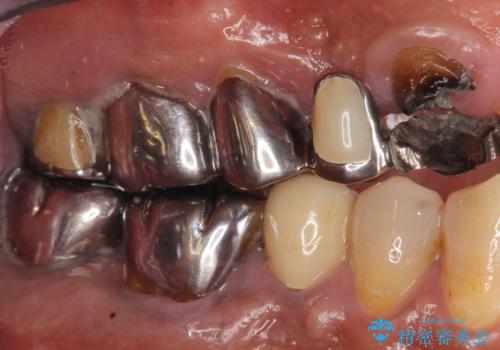

- 交通事故により前歯が折れたことを主訴に来院された患者様です。

精査したところ、前歯以外にも歯が折れており、上の歯の多くが保存不可能な状態でした。

インプラントと入れ歯の治療方針を提案したところ、なるべく予算を抑えたいとのことで入れ歯による治療をご希望されました。

保存可能な2本の歯を用いて、マグネットデンチャー(磁性アタッチメントを用いた入れ歯)による治療を行いました。